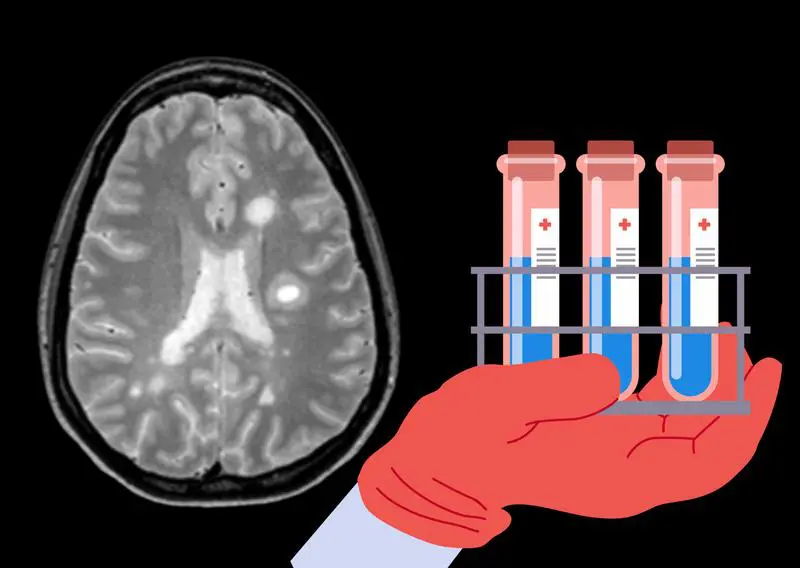

Quantitative analysis of beta-2 transferrin via Hydrasys 2Scan Focusing (Sebia) for the detection of CSF leaks

A CSF leak is a serious medical disorder that potentially leads to life-threatening conditions like meningitis. One analytical method to detect such CSF leaks is the measurement of beta-2 transferrin in human bodily fluids via Hydrasys 2Scan Focusing (Sebia). While...